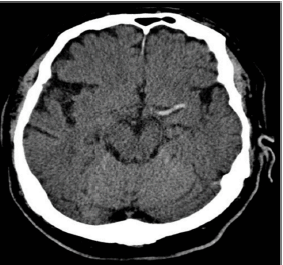

Procura pronto-socorro com queixa de déficit neurológico agudo, com aparecimento há 40 minutos. À admissão, exibe PA 150x92, FC 77, FR 18, SatO2 96% a.a., glicemia capilar de 90mg/dL. Ao exame neurológico, apresenta hemiplegia à direita, afasia global e paralisia facial de padrão central, com NIHSS = 15. Realizada TC de crânio, abaixo:

Neste momento, a conduta mais adequada para essa paciente seria